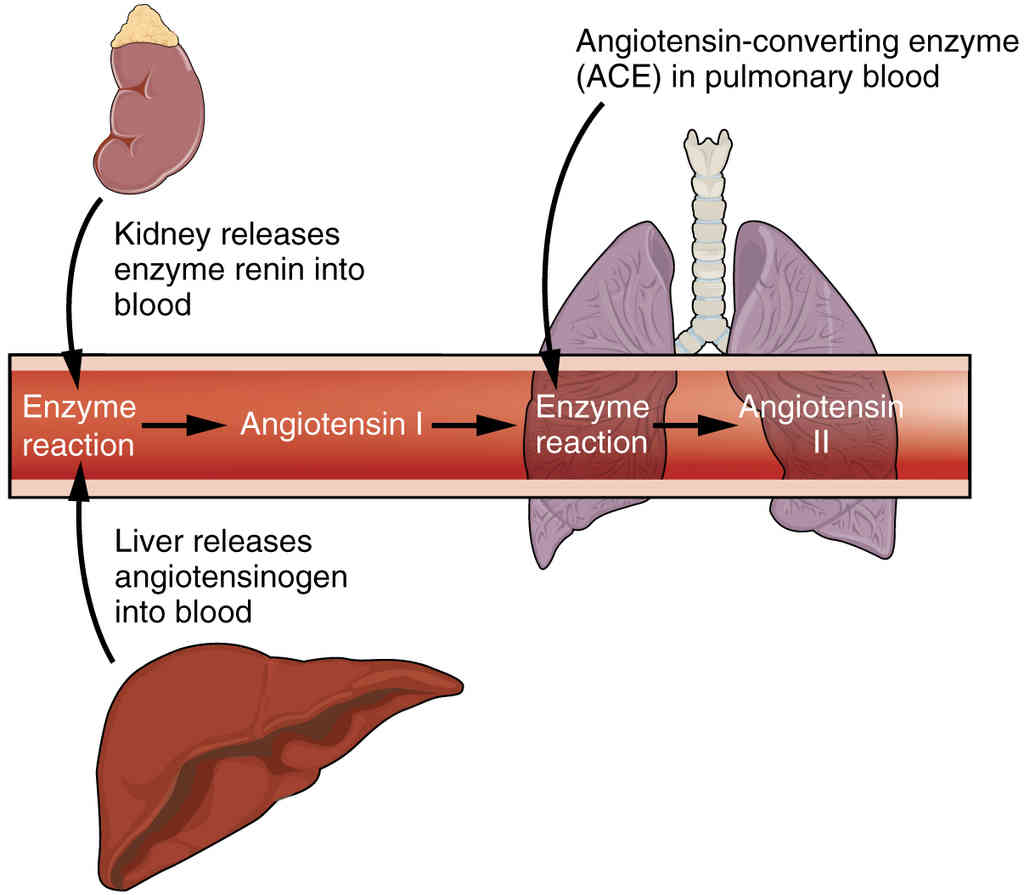

This page is under construction. For now, it is just a resource of the images found in the OpenStax Anatomy and Physiology Handbook. It wil slowly change into a revision tool. Each slide has a number. Use this to refer to the slide. When completed, it will have an unlabelled section, with labelled slides in parallel. On the unlabelled slides, write your answer and use the labelled slide to assess yourself. Keep track by also noting the number on each slide. Improvement at each attempt is important, more so than full marks on a first attempt.